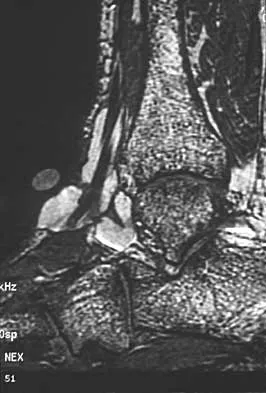

A 40-year-old woman has a symptomatic mass on the anterior aspect of the ankle. She reports no constitutional symptoms. An MRI scan is shown in Figure 12. What is the most likely diagnosis?

Explanation